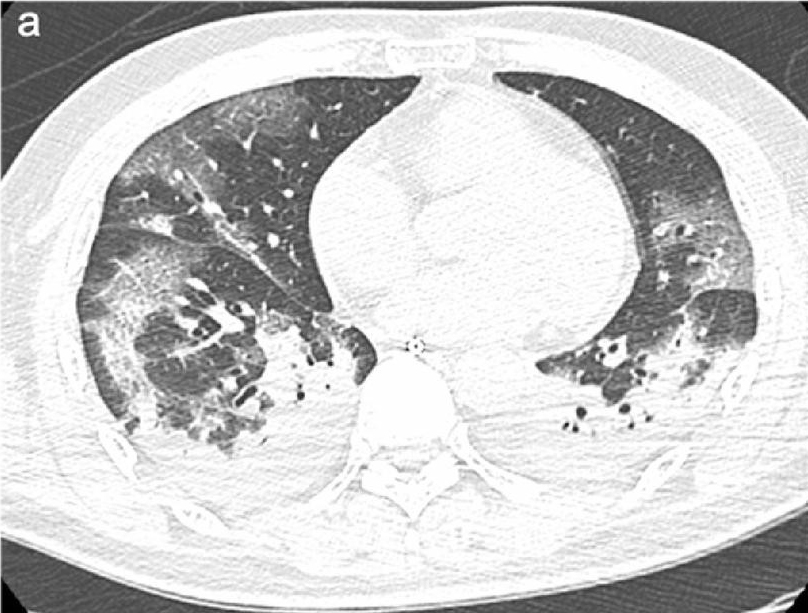

Sono immagini scioccanti quelle diffuse dai ricercatori dell'Istituto Nazionale per le Malattie Infettive Lazzaro Spallanzani di Roma in uno studio in via di pubblicazione sull'International Journal of Infectious Diseases. Sono le radiografie e le immagini della TAC dei polmoni appartenenti alle prime due persone risultate infette in Italia, due turisti cinesi in vacanza, e che dimostrano quanto può essere devastante il nuovo coronavirus.

I due pazienti, un uomo di 67 anni e una donna di 66, erano in forma e in salute. Seguivano solo una terapia orale per tenere a bada l'ipertensione. Dopo aver riscontrato problemi respiratori e febbre, la coppia è stata sottoposta a test di laboratorio che hanno confermato l'infezione con il virus SARS-CoV-2. Entrambi i pazienti hanno continuato ad aggravarsi fino a sviluppare la Sindrome da Distress Respiratorio Acuto (ARDS - Acute Respiratory Distress Syndrome).

Ci sono voluti solo quattro giorni per arrivare all'insufficienza respiratoria e due giorni dopo entrambi i pazienti respiravano solo grazie a un ventilatore. Le prime radiografie effettuate sui pazienti mostrano “opacità del vetro smerigliato”.

Lo studio ha anche scoperto che i vasi sanguigni che trasportano il sangue dal cuore ai polmoni per ossigenarsi si stavano allargando. Questa condizione, nota come ipertrofia, riduce lo spazio per l'aria, causando difficoltà respiratorie. È probabile che questo segno sia correlato all'iperemia - eccesso di sangue nei vasi polmonari - causato dall'infezione virale.

«I modelli polmonari in entrambi i pazienti sono caratterizzati da ipertrofia dei vasi polmonari, che sono aumentati di dimensioni, in particolare nelle aree con danno interstiziale più pronunciato», spiegano i ricercatori.